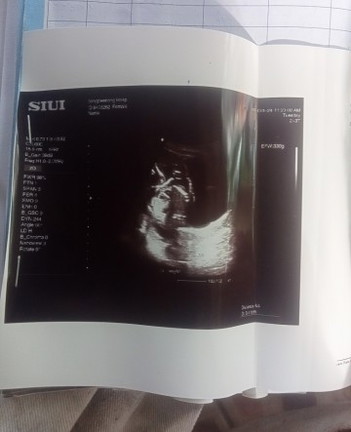

ซาวช่วง5เดือน หมอบอกน้องเอาขาบังไว้ เดาๆน่าจะเป็นผู้หญิงทำเพราะไม่เห็นจู๋

ตอนนี้จะเข้า8เดือนแล้ว ย้ายมาฝากโรงบาลใหม่ พรุ่งนี้หมอนัดไปซาว เราถามเรื่องเพศลูกได้มั้ยค่ะ